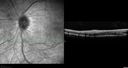

SPECTRALIS-SD-OCT SCAN: The OCT scan shows macular edema in both eyes with a serous macular detachment in the left eye. There are intraretinal cysts and retinal atrophy in the far periphery. The OCT scan does show atrophy of the outer retina.